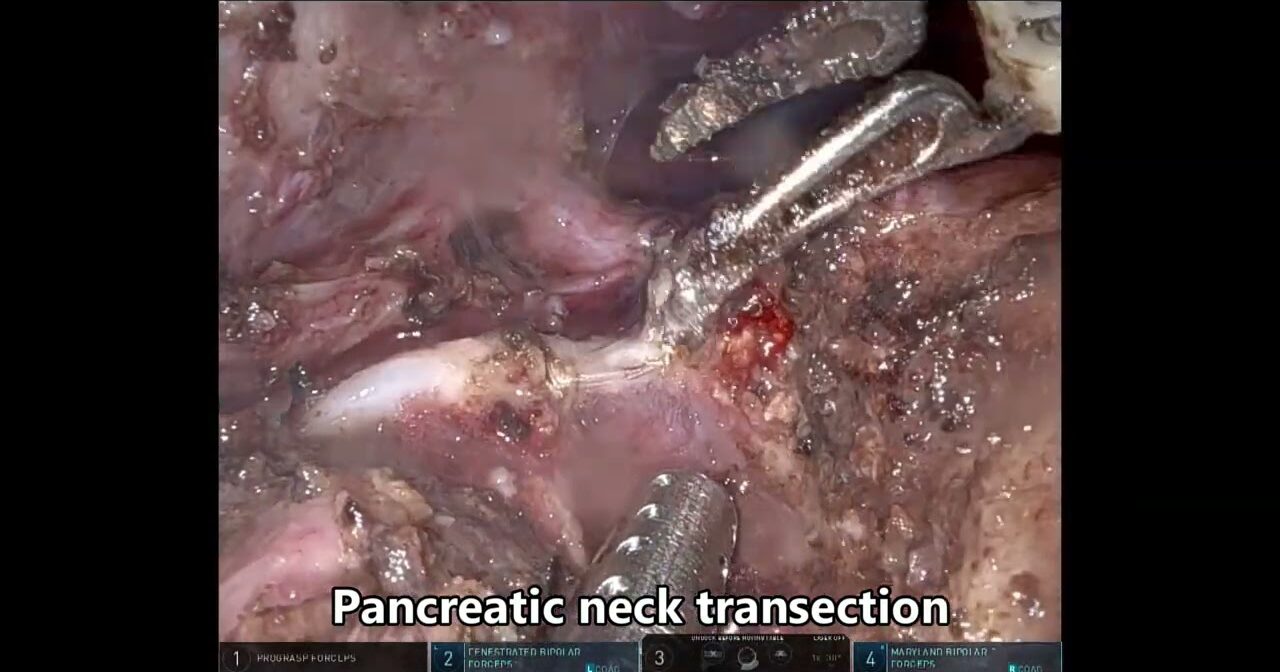

SAFE (Saline-Assisted Fascial Exposure) for Nerve-Sparing during RARP

Confocal Microscopy for Surgical Margins During Prostatectomy